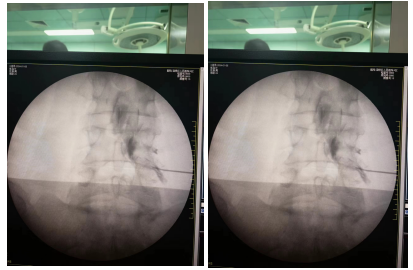

该患者腰椎间盘突出巨大、症状较重,但拒绝手术治疗,经副院长李翔带领科室疼痛组团队商讨后决定予以C臂引导下腰椎间盘胶原酶化学溶解术治疗。